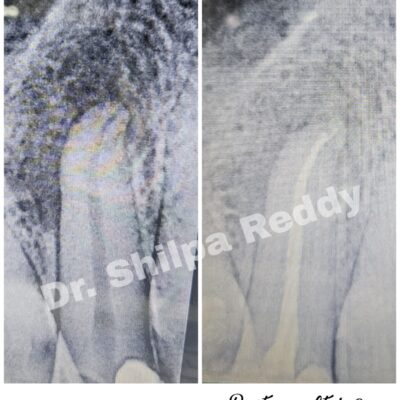

Trusted by dental clinics and hospitals for reliable, high-quality conservative, aesthetic and complex endodontic procedures

Specialized training in smile designing, complex root canal procedures, endodontic re-treatment, management of flare-ups, mishaps and emergencies.

With 10 years of experience in the field of Endodontics as well as Aesthetic dentistry, I collaborate with clinics to provide expertise in diagnosis, treatment planning and execution of complex cases in a streamlined, patient-friendly and affordable manner.

Streamlined endodontic protocols giving utmost importance to proper anaesthesia making procedures painless while maximizing efficiency.